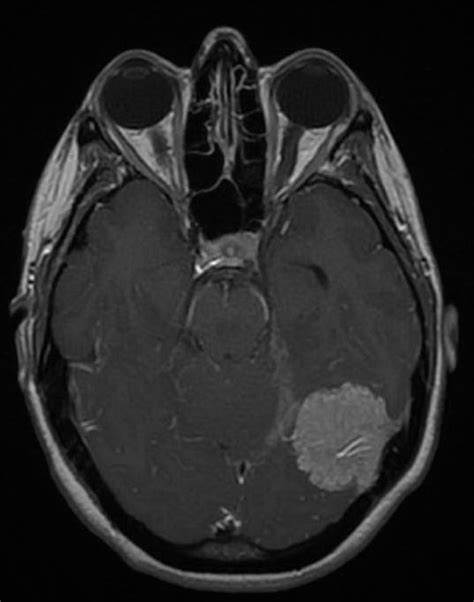

腦膜瘤是一種發(fā)生在腦膜(保護(hù)中樞神經(jīng)系統(tǒng)的膜層)上的腫瘤。雖然基因在其中起了作用,但它們發(fā)生的確切原因尚不清楚。

腦膜瘤的典型特征是占位小,但也有一小部分會(huì)變大。較小的腫瘤往往是良性的,甚至在人的一生中可能不會(huì)產(chǎn)生任何癥狀。然而,在某些情況下,當(dāng)腦膜瘤較大或?yàn)閻盒詴r(shí),癥狀明顯,可采用常規(guī)手術(shù)治療。腦膜瘤癥狀有哪些?腦膜瘤好治嗎?